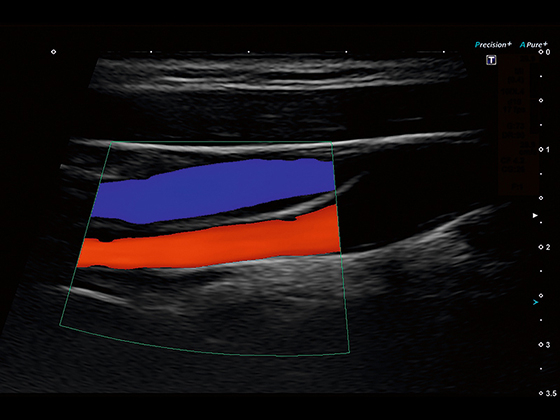

Кольорове допплерівське картування

Енергетичний допплерівський режим

Програма Dynamic Flow (надчутливий енергетичний допплер) *